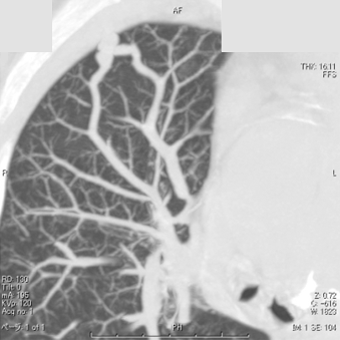

肺動静脈瘻

(肺動脈奇形)のCT

肺動脈と肺静脈に

異常な吻合が描出されている